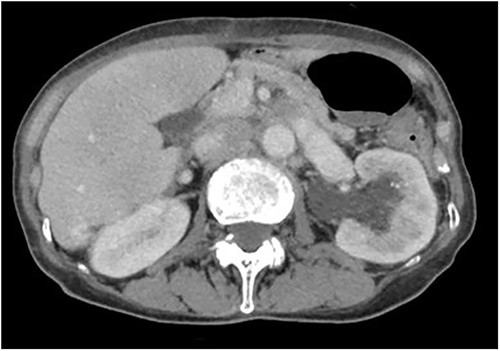

Forty-five days after the stent placement, the patient visited the emergency department complaining of fever and hematuria. CT showed that the left hydronephrosis had reappeared, and the lower end of the stent had migrated into the ureter (Fig. 3a and b). Blood tests revealed a worsening of renal function and a prominently elevated inflammatory response. Due to the diagnosis of relapse of left obstructive acute pyelonephritis caused by the migration of the ureteral stent, an emergency nephrostomy was performed promptly, and antibiotic treatment was started. The patient was discharged after 2 weeks of hospitalization.

Abdominal CT scan; (a) CT demonstrates the position of proximal coil formation in the left renal pelvis; (b) CT demonstrates proximal stent migration into the ureter.